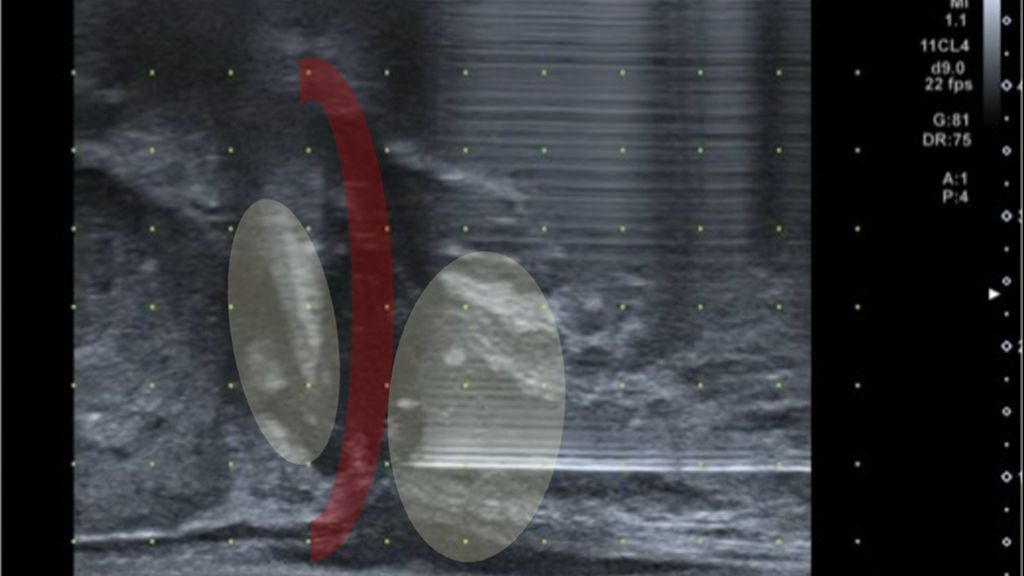

Abb. 2: Sonografische Darstellung der tiefen Beckenbodenmuskulatur (rot) und der Prostataapex. In Gelb dargestellt sind die Applikationsorte der tiefen Lokalanästhesie vor perinealer Prostatabiopsie

Für eine schmerzarme Biopsie ist eine Lokalanästhesie notwendig. In der Regel werden 5–7ml Lokalanästhetikum (z.B. Mepivacain 1%) bei 11 und 1 Uhr oberhalb des Anus subkutan injiziert. Zusätzlich sollte eine tiefergehende Anästhesie der Beckenbodenmuskulatur erfolgen (Musculus transversus perinei superficialis, Musculus levator ani), mit weiteren 5–10ml Lokalanästhetikum je Seite (Abb. 2).